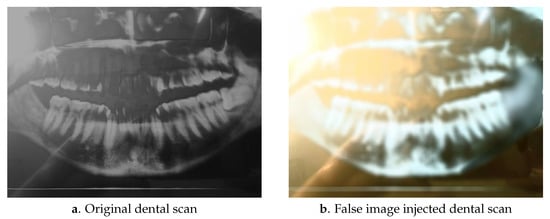

2. False Image Injection Attacks